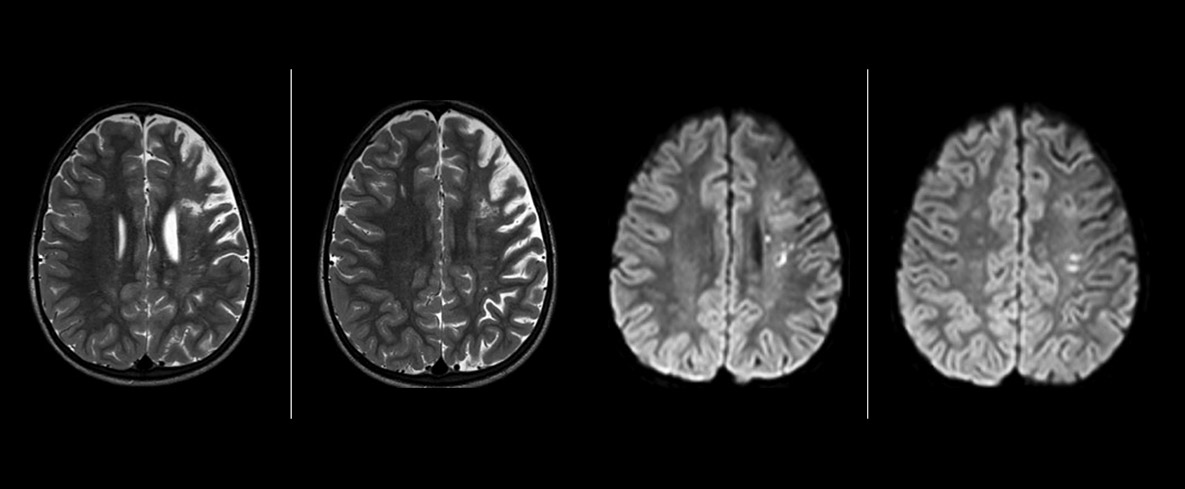

Pseudo-continuous arterial spin labeling (pCASL) was developed for brain perfusion imaging without contrast agent. “This is very desirable in pediatric patients where the general trend is to limit the administration of contrast,” says Dr. Miller. Growing confidence in specific applications “We built up confidence in pCASL by comparing it to contrast-based perfusion imaging. Once we had confidence that it was representing what the contrast perfusions were representing, we increased our diagnostic confidence by serial imaging in either the acute stage or the long term stages in a number of patients with arterial abnormalities.

Dr. Miller uses pCASL for all patients who present with chronic and acute cerebrovascular abnormalities such as acute stroke, as well as patients who present with signs of acute inflammation in the brain, and occasionally in patients with tumors, to assess the perfusion status of their tumor.

“In combination with diffusion weighted imaging, it can help give a more extended assessment of the degree of perfusion abnormality in a patient who is suffering acute ischemia. We have a number of patients who have chronic arterial insufficiency due to prior arterial abnormalities or acquired arterial abnormalities such as sickle cell disease or neurofibromatosis. Sometimes the child’s first manifestation of disease progression is a reduction in brain perfusion before stroke symptoms manifest clinically or in diffusion weighted imaging. We use pCASL to help delineate the perfusion abnormality.”

To other new users I would recommend to also start to interpret the pCASL images in comparison with other standard imaging – T2 and FLAIR and DWI – until the user gains confidence in interpreting these images by themselves.” “A powerful use of pCASL is in patients with chronic cerebrovascular stenosis, where clinicians desire information on how compensatory mechanisms of the brain are performing to enable perfusion to the brain. Often clinicians take into account how the compensatory mechanisms appear to help to provide adequate perfusion to the patient’s brain, and they may intervene surgically or make some other management decision.” “Another special application is the assessment of cerebrovascular reactivity with a Diamox perfusion exam, where we subtract two sets of pCASL images.”

“pCASL has now become more of a first-line scan for assessing perfusion for us, as opposed to DSC-based perfusion imaging with contrast agent. And in patients who were not planned to have contrast, we can perform pCASL for perfusion imaging without need to stop the exam, pull the patient out, and put in an IV. It also negates the postprocessing that’s necessary for dynamic susceptibility contrasts. And it allows us to repeat perfusion imaging in the same patient at the same imaging time, which is helpful in terms of patient motion, or in a situation where a scan needs to be done before pharmacological perfusion imaging.”